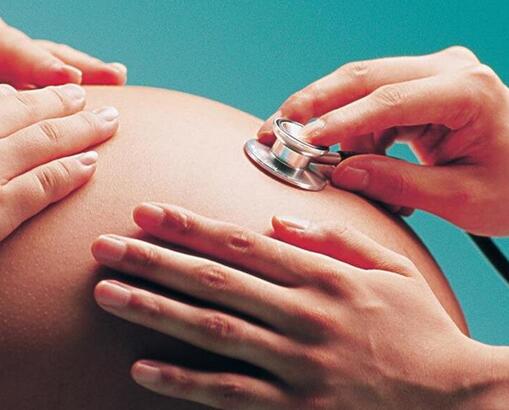

二、胎儿缺氧的表现-胎心异常

正常情况下,胎儿的胎心率是有规律的,约为每分钟120-160次。孕妇可以借助胎心监测仪观察胎儿胎心情况。若胎心异常,则应间隔20分钟再听,如胎心过快,还应在没有胎动时复听。若胎心超过160次/分,为胎儿早期缺氧的信号;胎心少于120次/分甚至胎心停止,则为胎儿缺氧晚期。